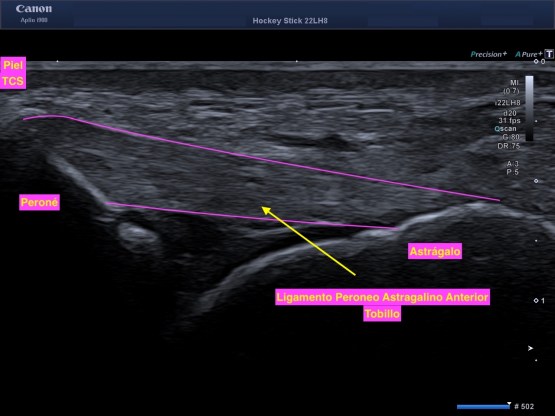

4. Ligamentos: Son bandas de tejido conjuntivo denso muy fuerte y elástico que une los huesos entre si en una articulación. Son hiperecogénicos.